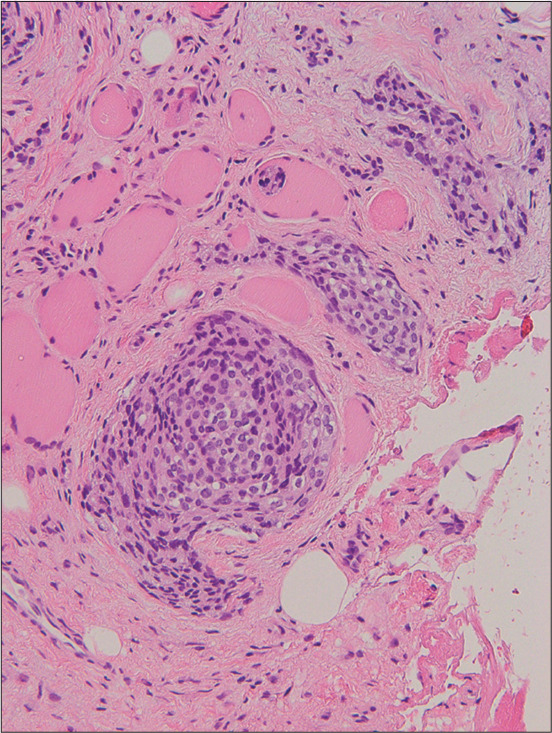

We report a case of a 73-year-old woman presenting with intracranial and extracranial meningioma with perineural spread crossing the foramen rotundum and pterygopalatine fossa, primarily along the maxillary nerve. She visited our hospital with the chief complaint of the left cheek swelling. Subsequent magnetic resonance imaging revealed a well-demarcated mass containing intracranial (cavernous sinus, Meckel's cave, and middle cranial fossa) and extracranial components (pterygopalatine fossa, orbit, nasal cavity, ethmoid and sphenoid sinuses, infratemporal fossa, and buccal space) through the foramen rotundum. A biopsy specimen was obtained from the cheek mass, and the histopathological diagnosis was meningothelial meningioma.